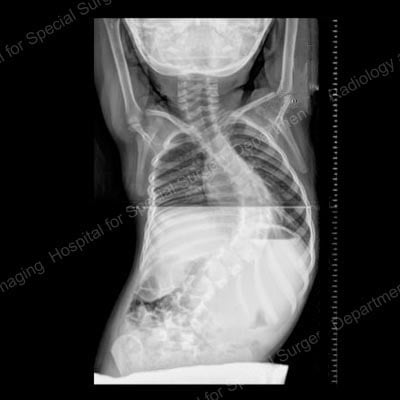

Figure 1. Posteroanterior (back-to-front) X-ray showing curvature of the spine in a patient with scoliosis